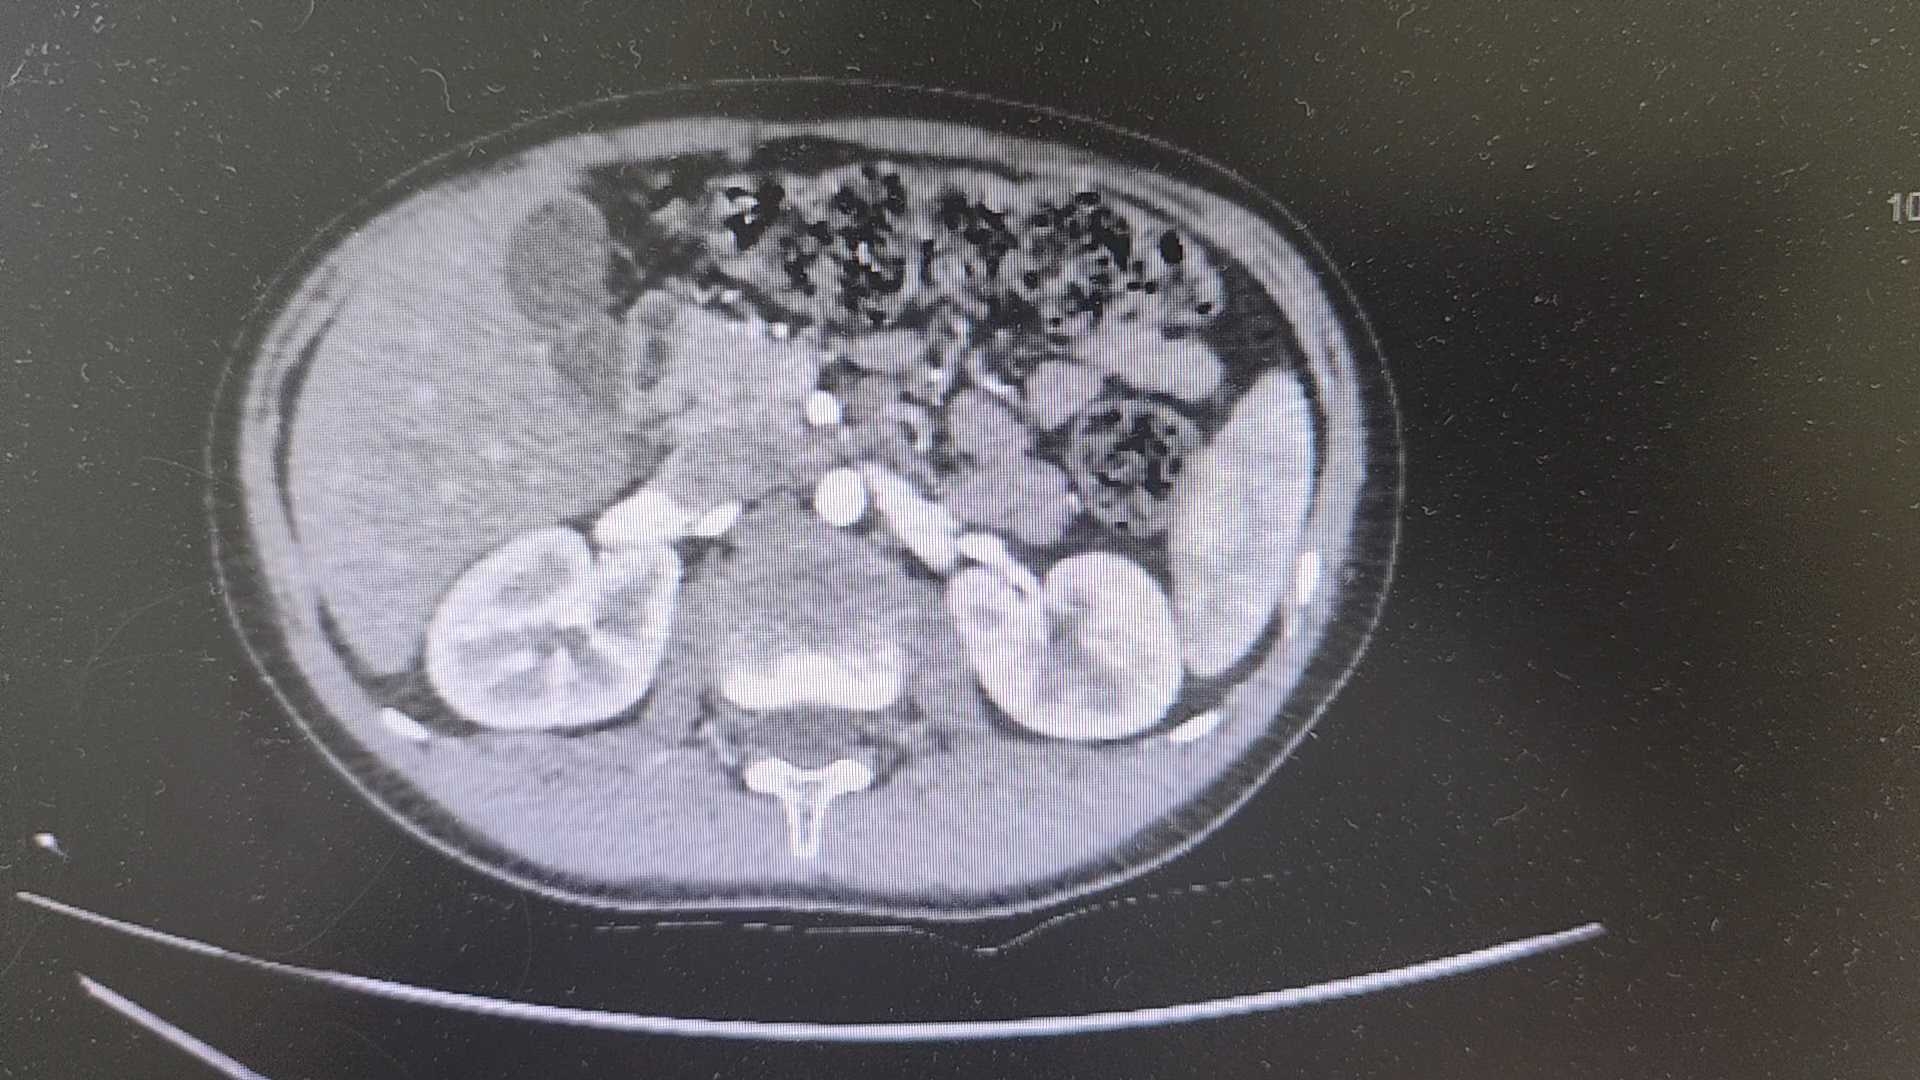

【检查】:

【临床诊断】:1.消化道出血,美克尔憩室?2.中度贫血3.腹腔积液